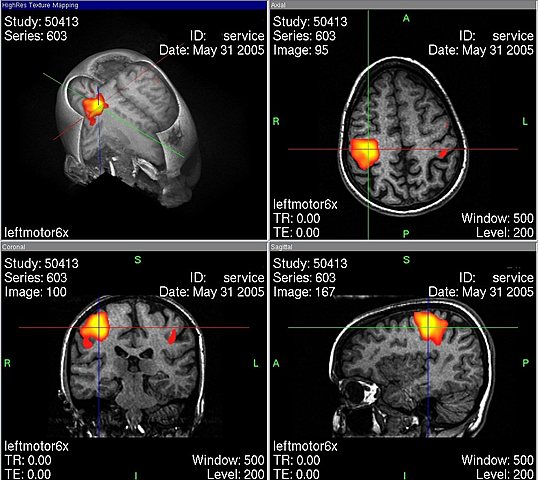

• El origen de la Resonancia Mágnetica

El origen de la Resonancia Mágnetica

El doctor Raymond Damadian demostró que la resonancia magnética podía ser usada para detectar enfermedades porque distintos tipos de tejidos emiten señales que varían en su duración, en respuesta al campo magnético.